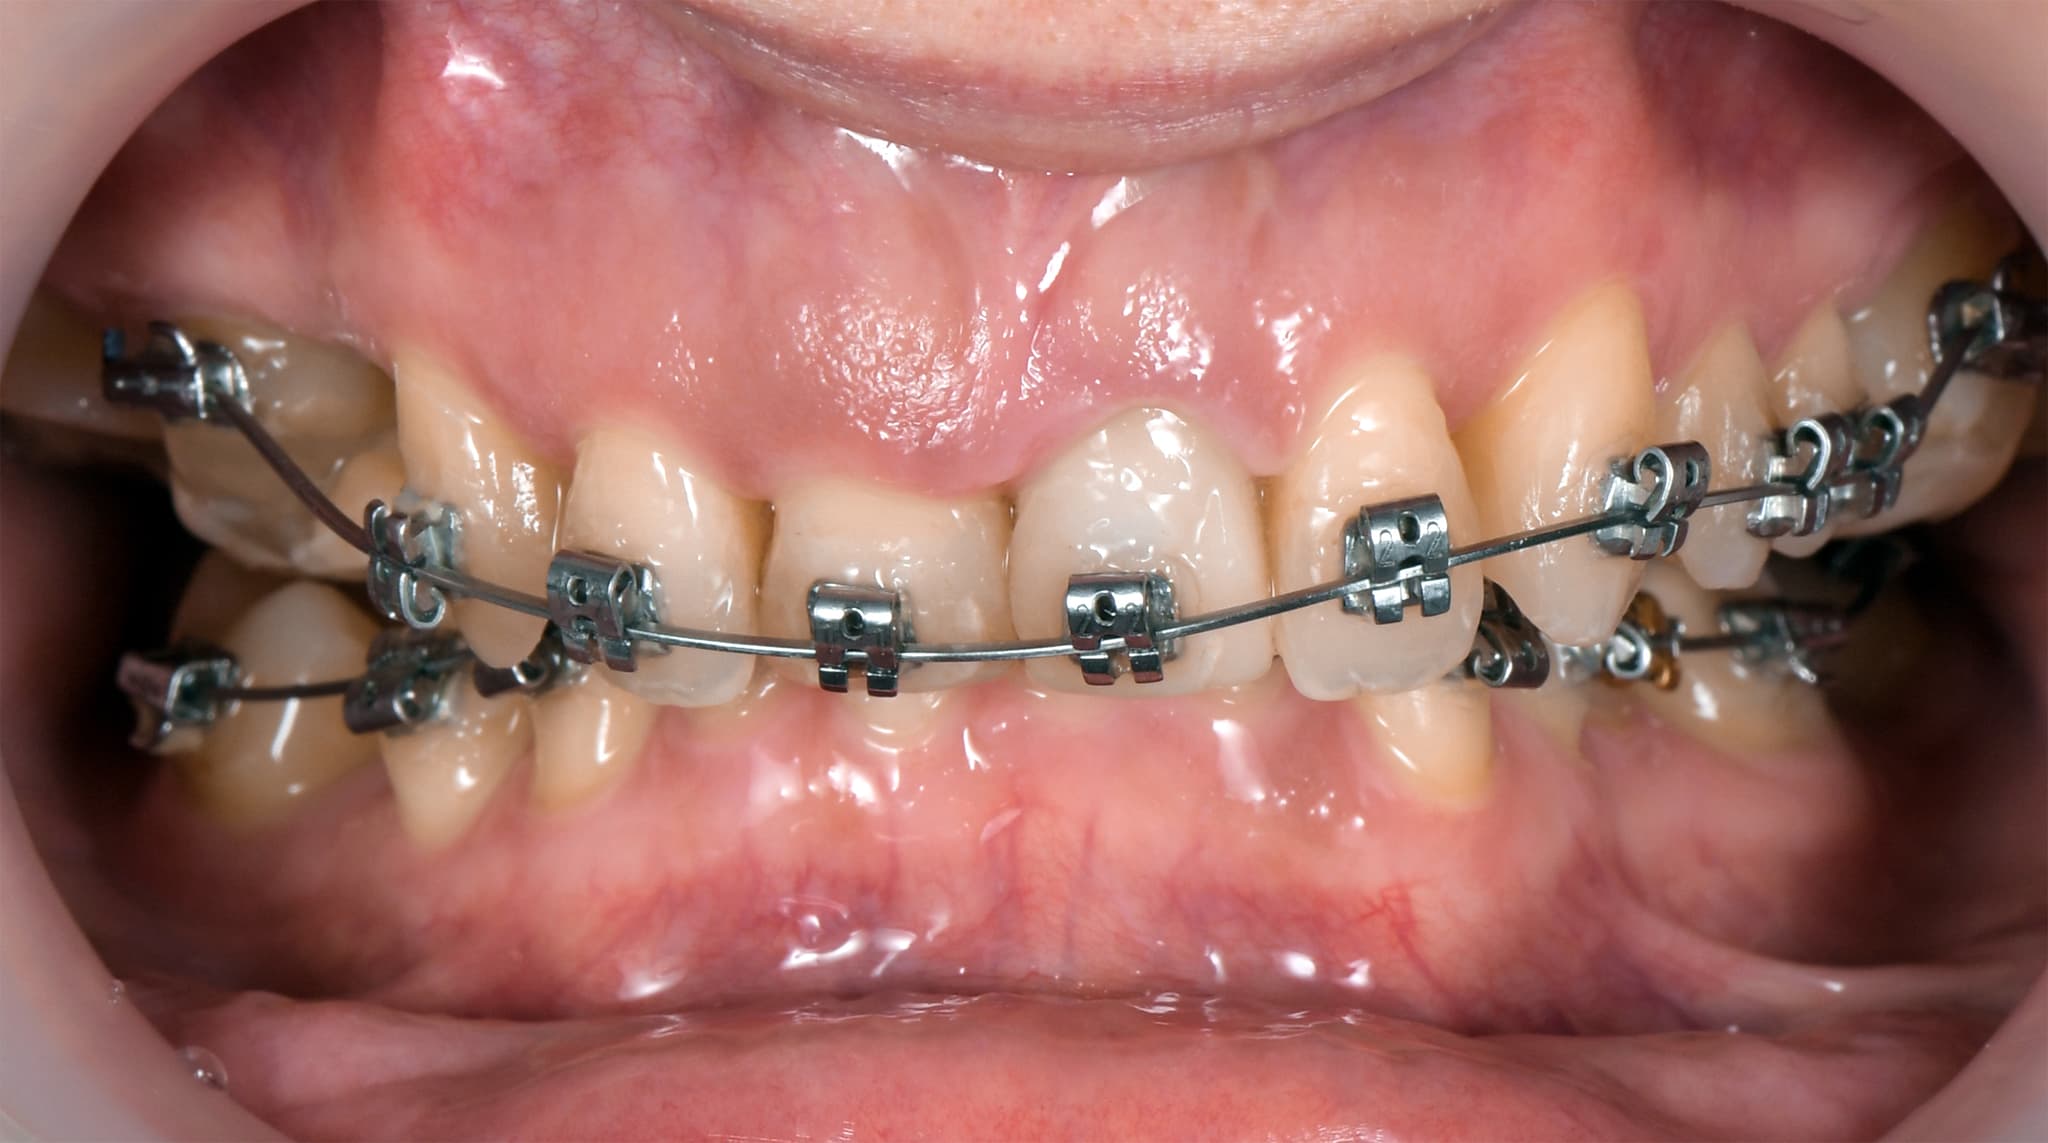

2. Active Treatment Phase

Movement with purpose.

Once the plan is validated, we begin the active treatment phase. Whether using aligners or fixed appliances, every step is informed by the final design. We move teeth to reduce the need for prosthetic intervention, align gingival levels for future esthetics, and sometimes use implants as anchorage for faster, more efficient results. The goal is to minimize invasive work and maximize synergy.